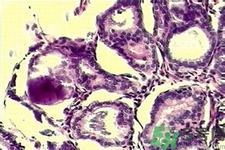

與良性乳腺增生鈣化相比,惡性乳腺增生鈣化群平均密度較低,密度及大小對(duì)乳腺疾病良惡性鑒別價(jià)值較大。乳腺X線片中微小鈣化分布似乎無(wú)規(guī)律可循,但病理發(fā)現(xiàn)癌腫發(fā)生于末梢導(dǎo)管時(shí),鈣化可位于大片壞死組織中或癌細(xì)胞間,亦可存在于所屬上級(jí)導(dǎo)管內(nèi)或?qū)Ч芊植嫣幓蛳噜徬倥萸粌?nèi)。